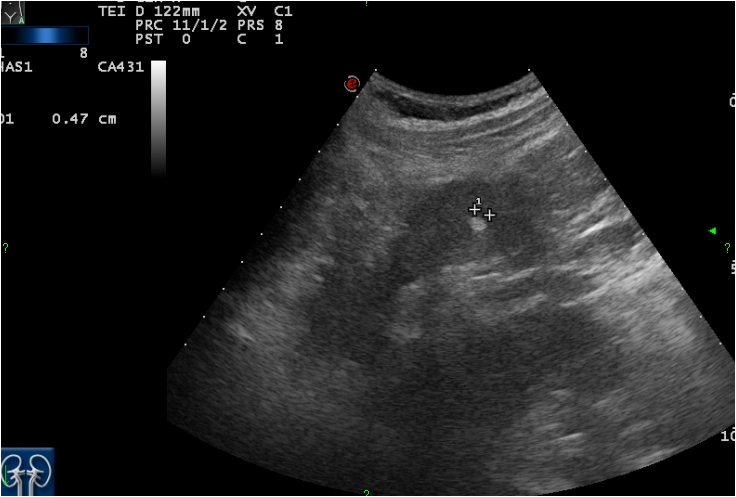

Die Ultraschalluntersuchung Sonografie ist meist die erste bildgebende Untersuchung bei Verdacht auf Blasenkrebs. Die Klassifikation Stadieneinteilung oder Staging genannt ist ein wichtiger Baustein für die Wahl der optimalen Therapie. Dabei kann der Arzt Blase Nieren und Harnwege begutachten.

Eine Ultraschalluntersuchung ermöglicht auch Blasensteine oder einen Blasentumor zu entdecken. Wirken Lymphknoten verdächtig veranlassen Ärzte in der Regel eine Biopsie oder Lymphknotenentnahme. Per Ultraschall lassen sich auch mögliche andere Ursachen für Beschwerden erkennen beispielsweise Nieren- Blasen-. Blasenkrebs kann als Folge einer Strahlentherapie entstehen. Blasenkrebs Mit der Diagnose Blasenkrebs hat der Patient nicht gerechnet. Sofern der Verdacht auf Blasenkrebs besteht nimmt der Arzt eine gründliche Untersuchung vor. Sie stellt zusammen mit der Biopsie Gewebeprobeentnahme die wichtigste Untersuchung für die Diagnose von Blasenkrebs dar. Ziel der Diagnostik ist eine möglichst frühzeitige Diagnosestellung und die Erhärtung oder Ausräumung des Verdachts auf Blasenkrebs. So stellen Ärzte beispielsweise bei Patienten mit einem Gebärmuttertumor ein erhöhtes Risiko für.

Die wichtigste Untersuchung zur Diagnose-Stellung ist die Spiegelung der Harnblase die sogenannte Zystoskopie. Es gibt keine Tumormarker im Blut die spezifisch für Blasenkrebs sind. Per Tastuntersuchung nimmt er dabei die Nierengegend den Unterbauch und die Geschlechtsorgane unter die Lupe. Blasenkrebs Mit der Diagnose Blasenkrebs hat der Patient nicht gerechnet. Liegt ein invasiver Harnblasentumor vor sind tiefgreifende Maßnahmen nötig. Wirken Lymphknoten verdächtig veranlassen Ärzte in der Regel eine Biopsie oder Lymphknotenentnahme. Die Ultraschalluntersuchung Sonografie ist meist die erste bildgebende Untersuchung bei Verdacht auf Blasenkrebs.